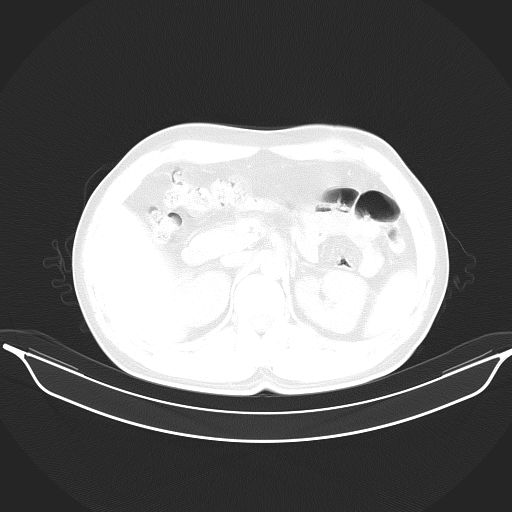

标题: CT25490:男,40岁,体检发现;无其它不适。 [打印本页]

标题: CT25490:男,40岁,体检发现;无其它不适。

考虑:1、过各敏性肺炎可能性大,建议定期复查。

2、轻度脂肪肝。

考虑右下肺周围性肺癌并肺内多发转移,纵隔淋巴结转移!

支持 !考虑右下肺周围性肺癌并肺内多发转移,纵隔淋巴结转移,(气管前腔静脉后,隆突下,主动脉弓下都有了)